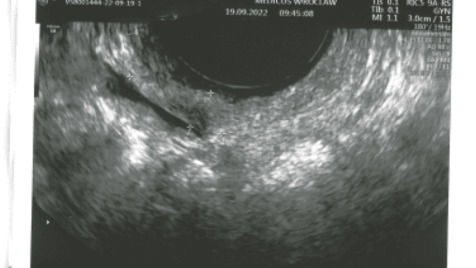

nawet nie wiem od czego zacząć, więc mówią, że wtedy najlepiej od początku... Zatem ENDOMETRIOZA, mianowicie ból, strach, załamania nerwowe problem z wiarygodnością "znowu Cię boli, znów z nami nie pójdziesz" udowadnianie lekarzom,że naprawdę coś się ze mną dzieje i tak od 16 roku życia żadnej diagnozy od problemów z miesiączkami po ich całkowite zatrzymania, przez terapie hormonalne, po niepotwierdzony IBS i mogłabym długo wymieniać, aż teraz po 12 latach szukania odpowiedzi w końcu dowiedziałam się co mi jest i rozpoczęła się moja walka o lepsze życie póki nie jest za późno. Oprócz Endometriozy (a dokładnie zmian endometrialnych) widocznych w rezonansie, mam jeszcze jednego lokatora w sobie - mięśniak wielkości 26x40x27 mm z boku macicy. Niestety endometrium przykleiło mi się już do jelita i planowana jest jego resekcja bym mogła normalnie funkcjonować.